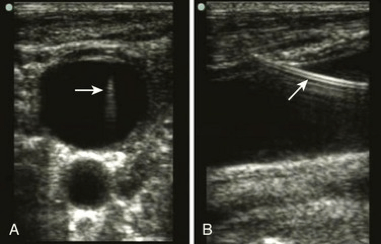

- Pro Tip: The US probe has to slide or fan forward in order to continue following the tip as the needle advances (see image). If the US probe does not move, you will end up looking the shaft of the needle instead of the needle tip. As a result, the needle tip can get deeper than intended which is a risk for pneumothorax and arterial puncture.

- Ultrasound is one of the simplest and most effective ways to confirm venous cannulation.1 Find the guide wire in the short-axis/transverse view. Slide the ultrasound to follow the wire into the vein, and continue to follow the wire to the clavicle to make sure it does not come out of the back wall of the vein into the artery. Turn the probe 90 degrees to confirm wire placement in the long axis view as well.